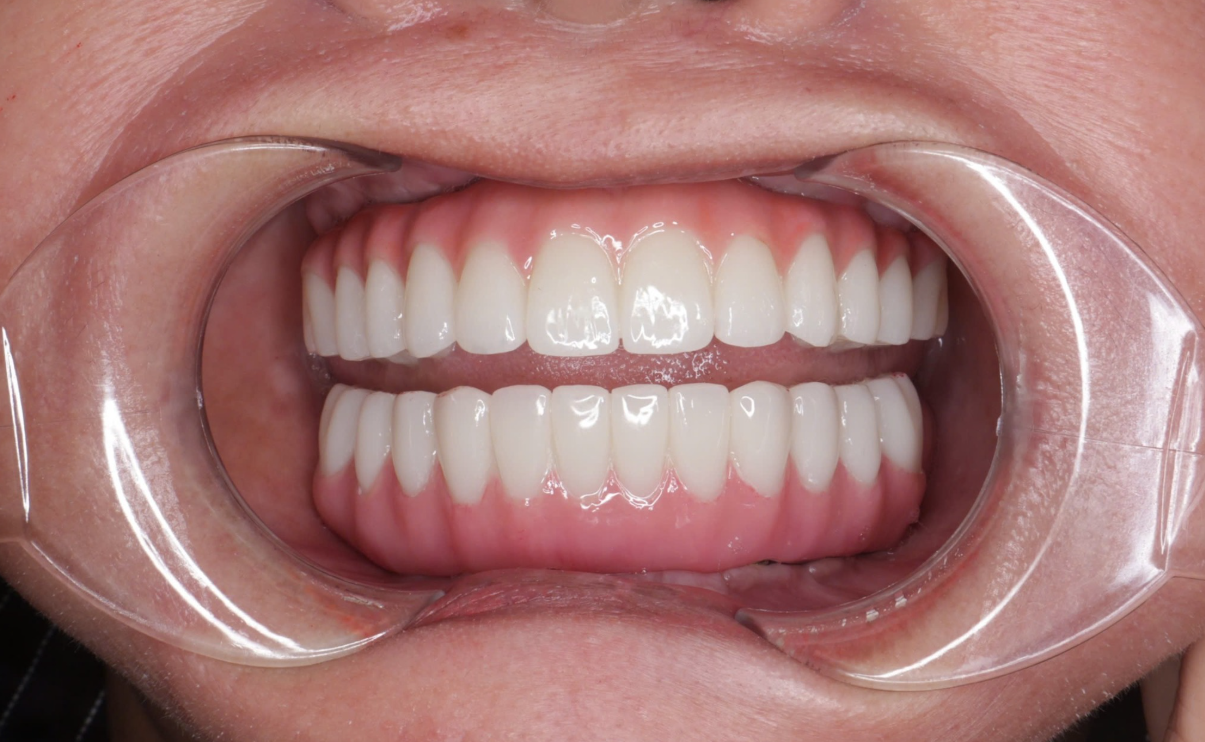

Tái lập thẩm mỹ nụ cười sau khi trồng răng toàn hàm.

Hàm IBar đạt thẩm mỹ rất cao, tự nhiên như răng thật.

Tính thẩm mỹ cao là ưu điểm lớn khi nhắc đến hàm toàn hàm Thimble.